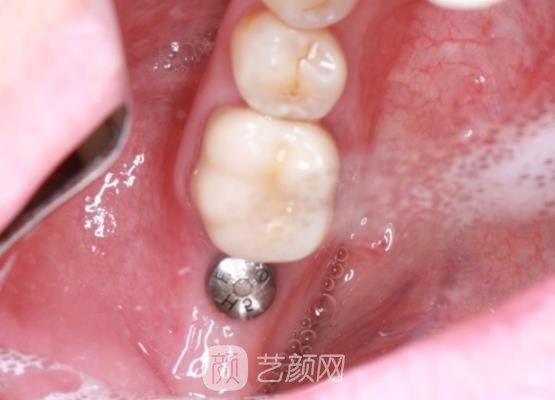

接下来手术就开始了,打麻药的时候是有一些疼的,但是后来麻药有了作用,疼痛的感觉就基本上没有了,只能感觉到我的牙龈处肌肉一直在动手术,短短几个小时以后就结束了,也是比较方便的,没有浪费我很多的时间,这是我没有想到的。

手术结束以后,我的牙龈处还有一些肿胀的情况,医生告诉我不用太过于担心,然后又叮嘱了我一些关于手术术后的相关注意事项,叮嘱我在饮食方面一定要注意不要吃一些过于坚固的食物,否则就会造成种植牙的松动,影响手术的成果。

几个月以后,我的牙齿已经恢复好了,口腔也没有什么异物的感觉,而且手术成果真的很自然,就像是我自己的牙齿一样,看不出来手术的痕迹,现在我终于可以大吃特吃了,哈哈。